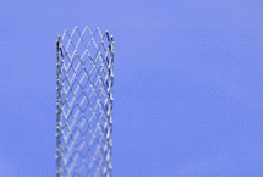

Стенты коронарные

В данную подсубпозицию включаются стенты коронарные, предназначенные для помещения внутрь пораженной части коронарного сосуда, где, расширяясь за счет эффекта «памяти» материала изготовления или с помощью баллона, выполняют функцию опорного каркаса для укрепления и поддержания стенок пораженного участка сосуда, обеспечивая нормальный кровоток по сосуду и нормальное кровоснабжение органа. Такие стенты могут быть изготовлены, например, в виде тонкой полой металлической или полимерной трубки

с ячейками либо из цельной круглой проволоки, которой сначала придается синусоидальная форма, а затем проводится спайка непрерывной синусоидальной конструкции. |

Примеры изображения стентов приведены ниже.